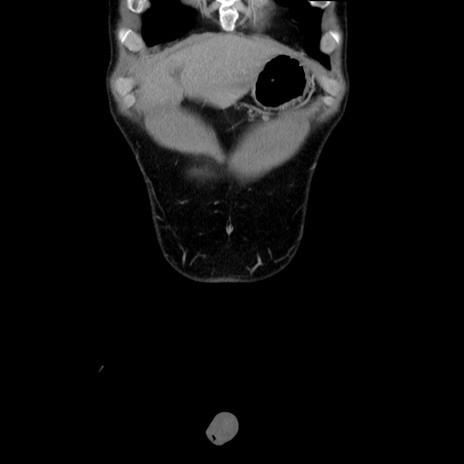

症例36(冠状断像)

【症例】20歳代 男性

【主訴】心窩部痛

【現病歴】今朝より上腹部痛あり。一旦軽快していたが再度出現したため救急要請。昨日夕に白身の魚を含む刺身を食べた。

【身体所見】BP 136/89mmHg、HR 74/min、BT 37.0℃、腹部:膨満、軟、心窩部に圧痛あり。反跳痛なし、筋性防御なし、腸雑音やや亢進あり。

【データ】WBC 17700、CRP 0.48